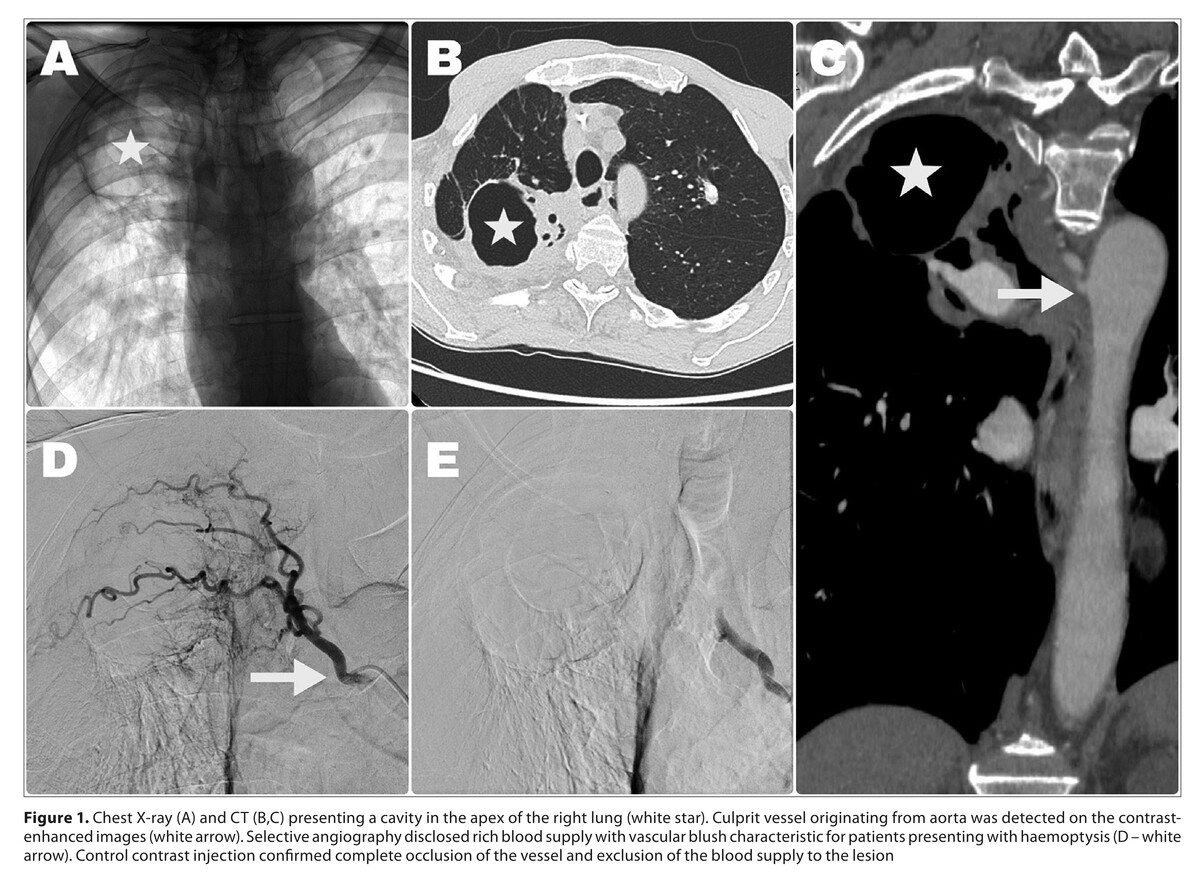

Aspergilloma is a disease characterized by the formation of saprophytic fungal colonies in pulmonary cavities. Haemoptysis is the most common clinical presentation which may range from mild to life-threatening. Treatment options include conservative management, surgical resection and bronchial artery embolization (BAE). Case Report. The case is described of a 66-year-old patient treated for haemoptysis due to aspergilloma for 6 years. Initially, the patient received conservative treatment, which did not yield measurable long-term benefits. He was later referred for minimally invasive treatment – bronchial artery embolization. Following embolization, symptoms reappeared after 5 years and the patient again underwent successful endovascular treatment. This case illustrates the superiority of minimally-invasive treatment over conservative therapy in managing haemoptysis.